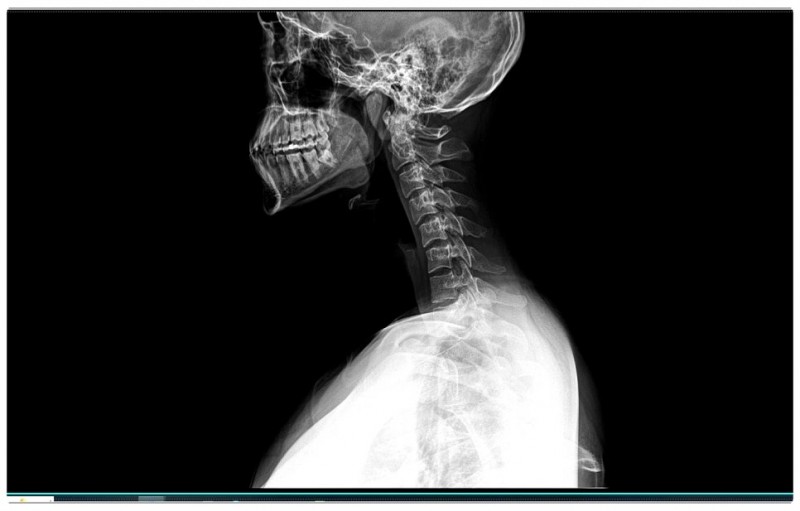

하지만 실제로는 거북목과 굽은 등이 함께 진행되는 경우가 많습니다.

특히 어깨 통증이나 팔로 방사되는 통증이 동반된다면,

턱관절이 살짝 틀어지면 바로 아래 목뼈 1번, 2번이 영향을 받습니다.

이 부분에서 균형이 무너지면 목은 앞으로 빠지고,

굽은 등이 만들어지죠.